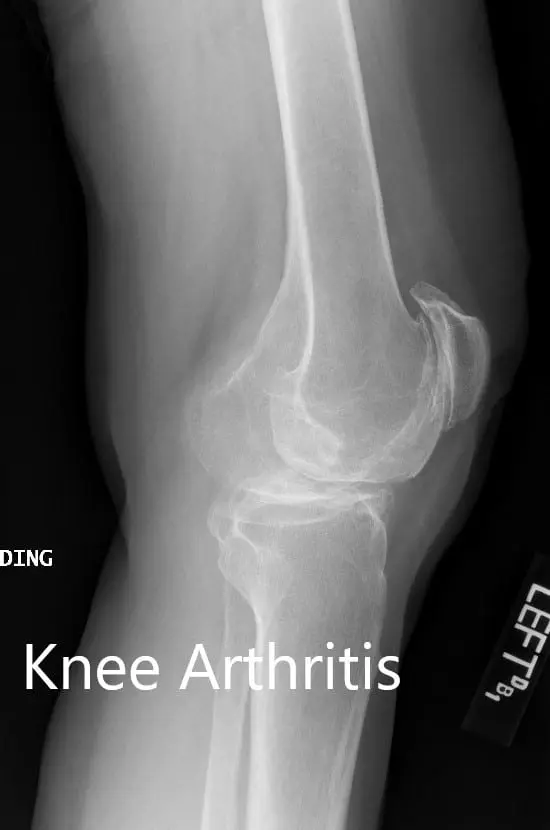

Preoperative X-ray showing the lateral views of the right and the left knee respectively

Preoperative X-ray showing the lateral views of the right and the left knee respectively - img 2

Preoperative X-ray showing the lateral views of the right and the left knee respectivelyComplete Orthopedics patient specific surgical plan for a Bilateral Custom Total Knee Replacement in a 61-year-old male with Knee Arthritis & Genu Valgum Deformity